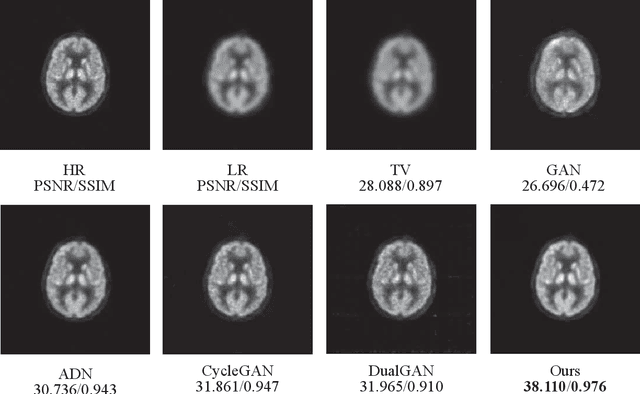

Abstract:Low resolution of positron emission tomography (PET) limits its diagnostic performance. Deep learning has been successfully applied to achieve super-resolution PET. However, commonly used supervised learning methods in this context require many pairs of low- and high-resolution (LR and HR) PET images. Although unsupervised learning utilizes unpaired images, the results are not as good as that obtained with supervised deep learning. In this paper, we propose a quasi-supervised learning method, which is a new type of weakly-supervised learning methods, to recover HR PET images from LR counterparts by leveraging similarity between unpaired LR and HR image patches. Specifically, LR image patches are taken from a patient as inputs, while the most similar HR patches from other patients are found as labels. The similarity between the matched HR and LR patches serves as a prior for network construction. Our proposed method can be implemented by designing a new network or modifying an existing network. As an example in this study, we have modified the cycle-consistent generative adversarial network (CycleGAN) for super-resolution PET. Our numerical and experimental results qualitatively and quantitatively show the merits of our method relative to the state-ofthe-art methods. The code is publicly available at https://github.com/PigYang-ops/CycleGAN-QSDL.